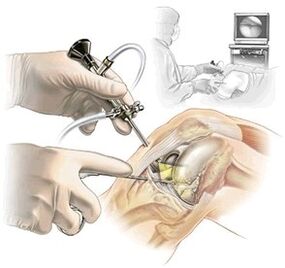

- artroscopia – efectuată în cazurile de leziune a meniscului, care provoacă dureri la genunchi pe interior. Această metodă este efectuată nu numai pentru diagnostic, ci și în timpul tratamentului;